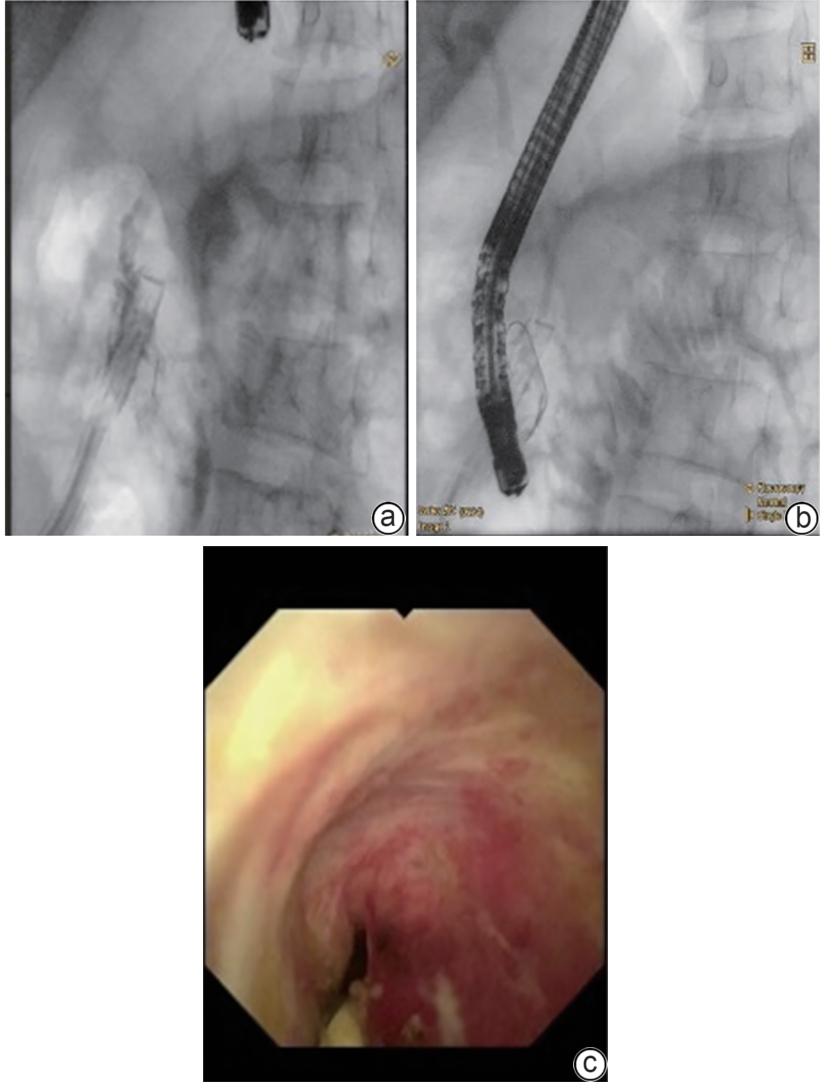

Successful treatment of biliary fistula after Beger surgery by oral choledochoscopy-assisted percutaneous-endoscopic rendezvous technique: A case report

Yuxin WANG, Weigang GU, Zheng JIN, Xiaofeng ZHANG

2025, 41(2): 333-336. DOI: 10.12449/JCH250220

Abstract(845) HTML (244) PDF (4794KB)(48)

Abstract:

Duodenum-preserving pancreatic head resection, also known as Beger surgery, has a high incidence rate of bile duct injury after surgery, while the treatment modality for bile duct injury depends on the severity of the injury, and endoscopic therapy is often challenging in case of severe bile duct injury. Recently a patient with biliary fistula after Beger surgery was admitted to Affiliated Hangzhou First People’s Hospital, Westlake University, and successful diagnosis and treatment were achieved through oral choledochoscopy-assisted percutaneous-endoscopic rendezvous technique.